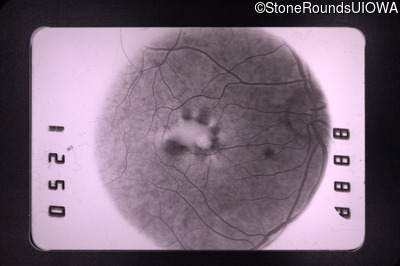

Fluorescein Angiography - Right - 20/30

Exemplar